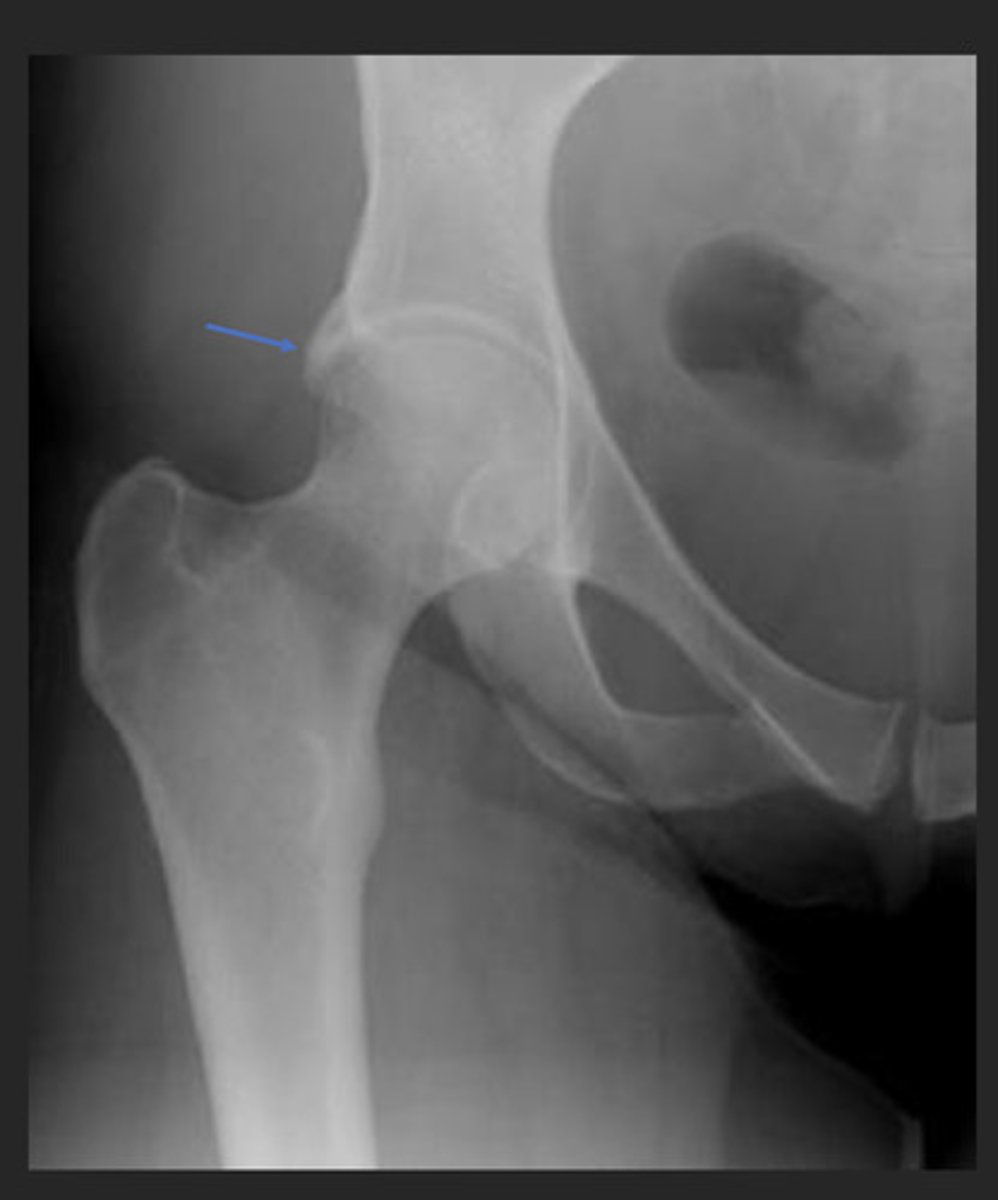

femoral acetabular impingement (FAI)

impingement between the femoral head/neck and acetabular rim

*occurs secondary to previous hip trauma/pathology with boney overgrowth (osteophytes)

TYPES:

1. cam

2. pincer

*most individuals have a combo of both

Cam type FAI

overgrowth of the femoral head/neck

Pincer type FAI

overgrowth of the acetabular rim